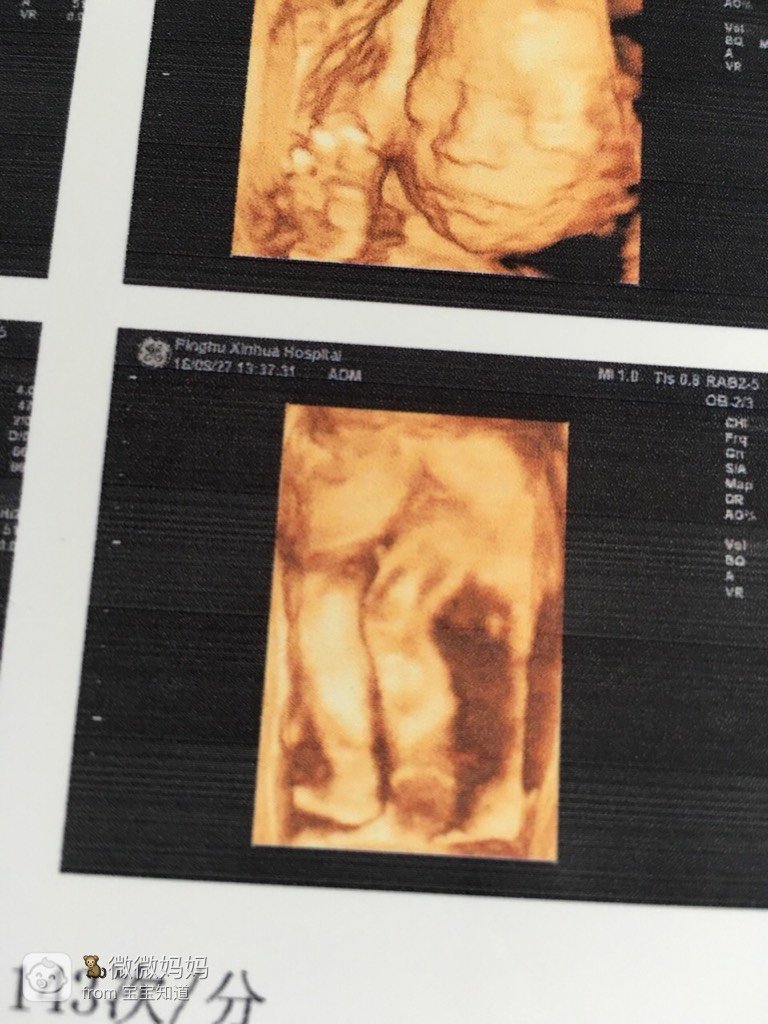

一个人常常会想宝宝长啥样呢。宝宝是否健康 是否府命某麻麻有时候会情绪化影响到你没有。各种猜辉然想件惠。每当麻麻看到肚子里的你 就好期待马上迎接你的到来 这样是不是麻麻情绪低落时影响不到你了。